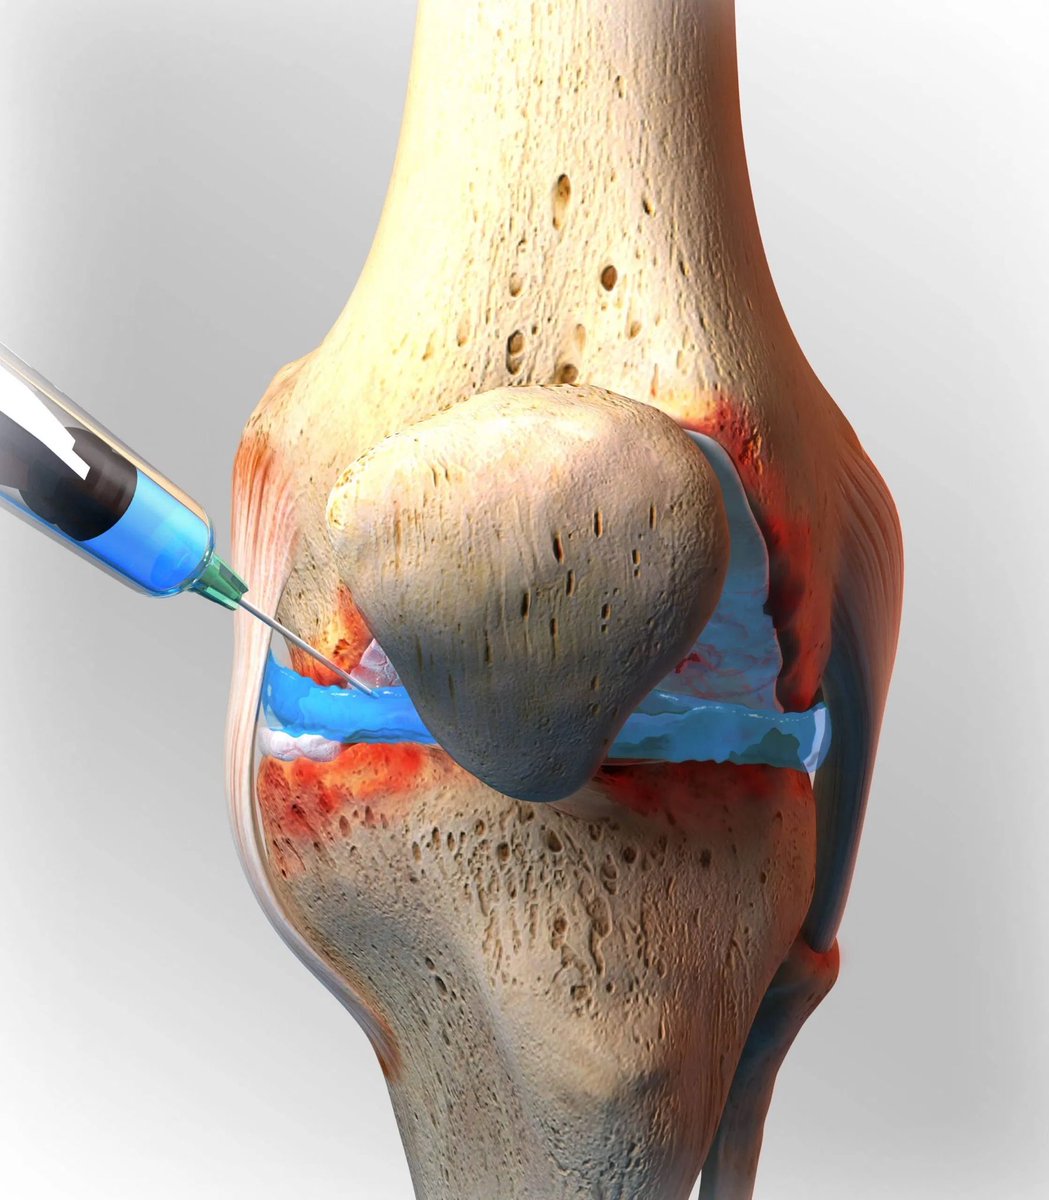

- بعض الادوية والمكملات الغذائية وكذلك الحقن الموضعية قد تعيد بناء الغضروف وتمنع تطور خشونة المفاصل .

الحقن الموضعية والمكملات الغذائية لا تعالج الخشونة ولا تعيد بناء الغضاريف كما أن تأثيرها مقتصر على تخفيف الألم وتختلف الاستجابة لها من مريض لآخر .

- حقن المفصل بالخلايا الجذعية يعمل على بناء الغضاريف الهلاليه ويعيد ترميمها ويحد من خشونة المفاصل .

فيما يخص الخلايا الجذعية أصدرت الجمعية السعودية لجراحة العظام بيانا تفصيليا بذلك وأوضحت انها لازالت قيد الدراسة و البحث ولاتنصح بعمل مثل ذلك .